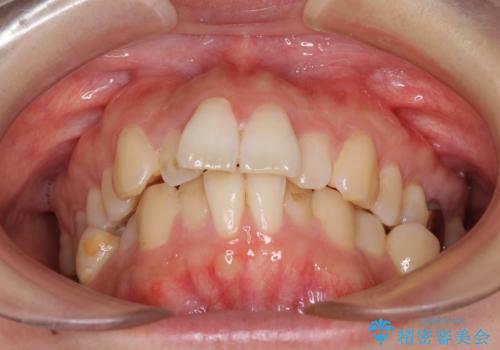

- 前歯のデコボコを気にして来院された患者様です。

非抜歯矯正にて治療を行うと、仕上がりで口元が突出する可能性があったため、小臼歯抜歯での矯正治療を行うこととしました。

上顎は左右の第一小臼歯2本を、下顎は左右の第二小臼歯2本を抜歯して、口元が突出しないようにしながら、奥歯の咬み合わせを改善していく治療計画としました。

目立たない装置が希望であったため、上顎が裏側装置である、ハーフリンガル装置を選択されました。